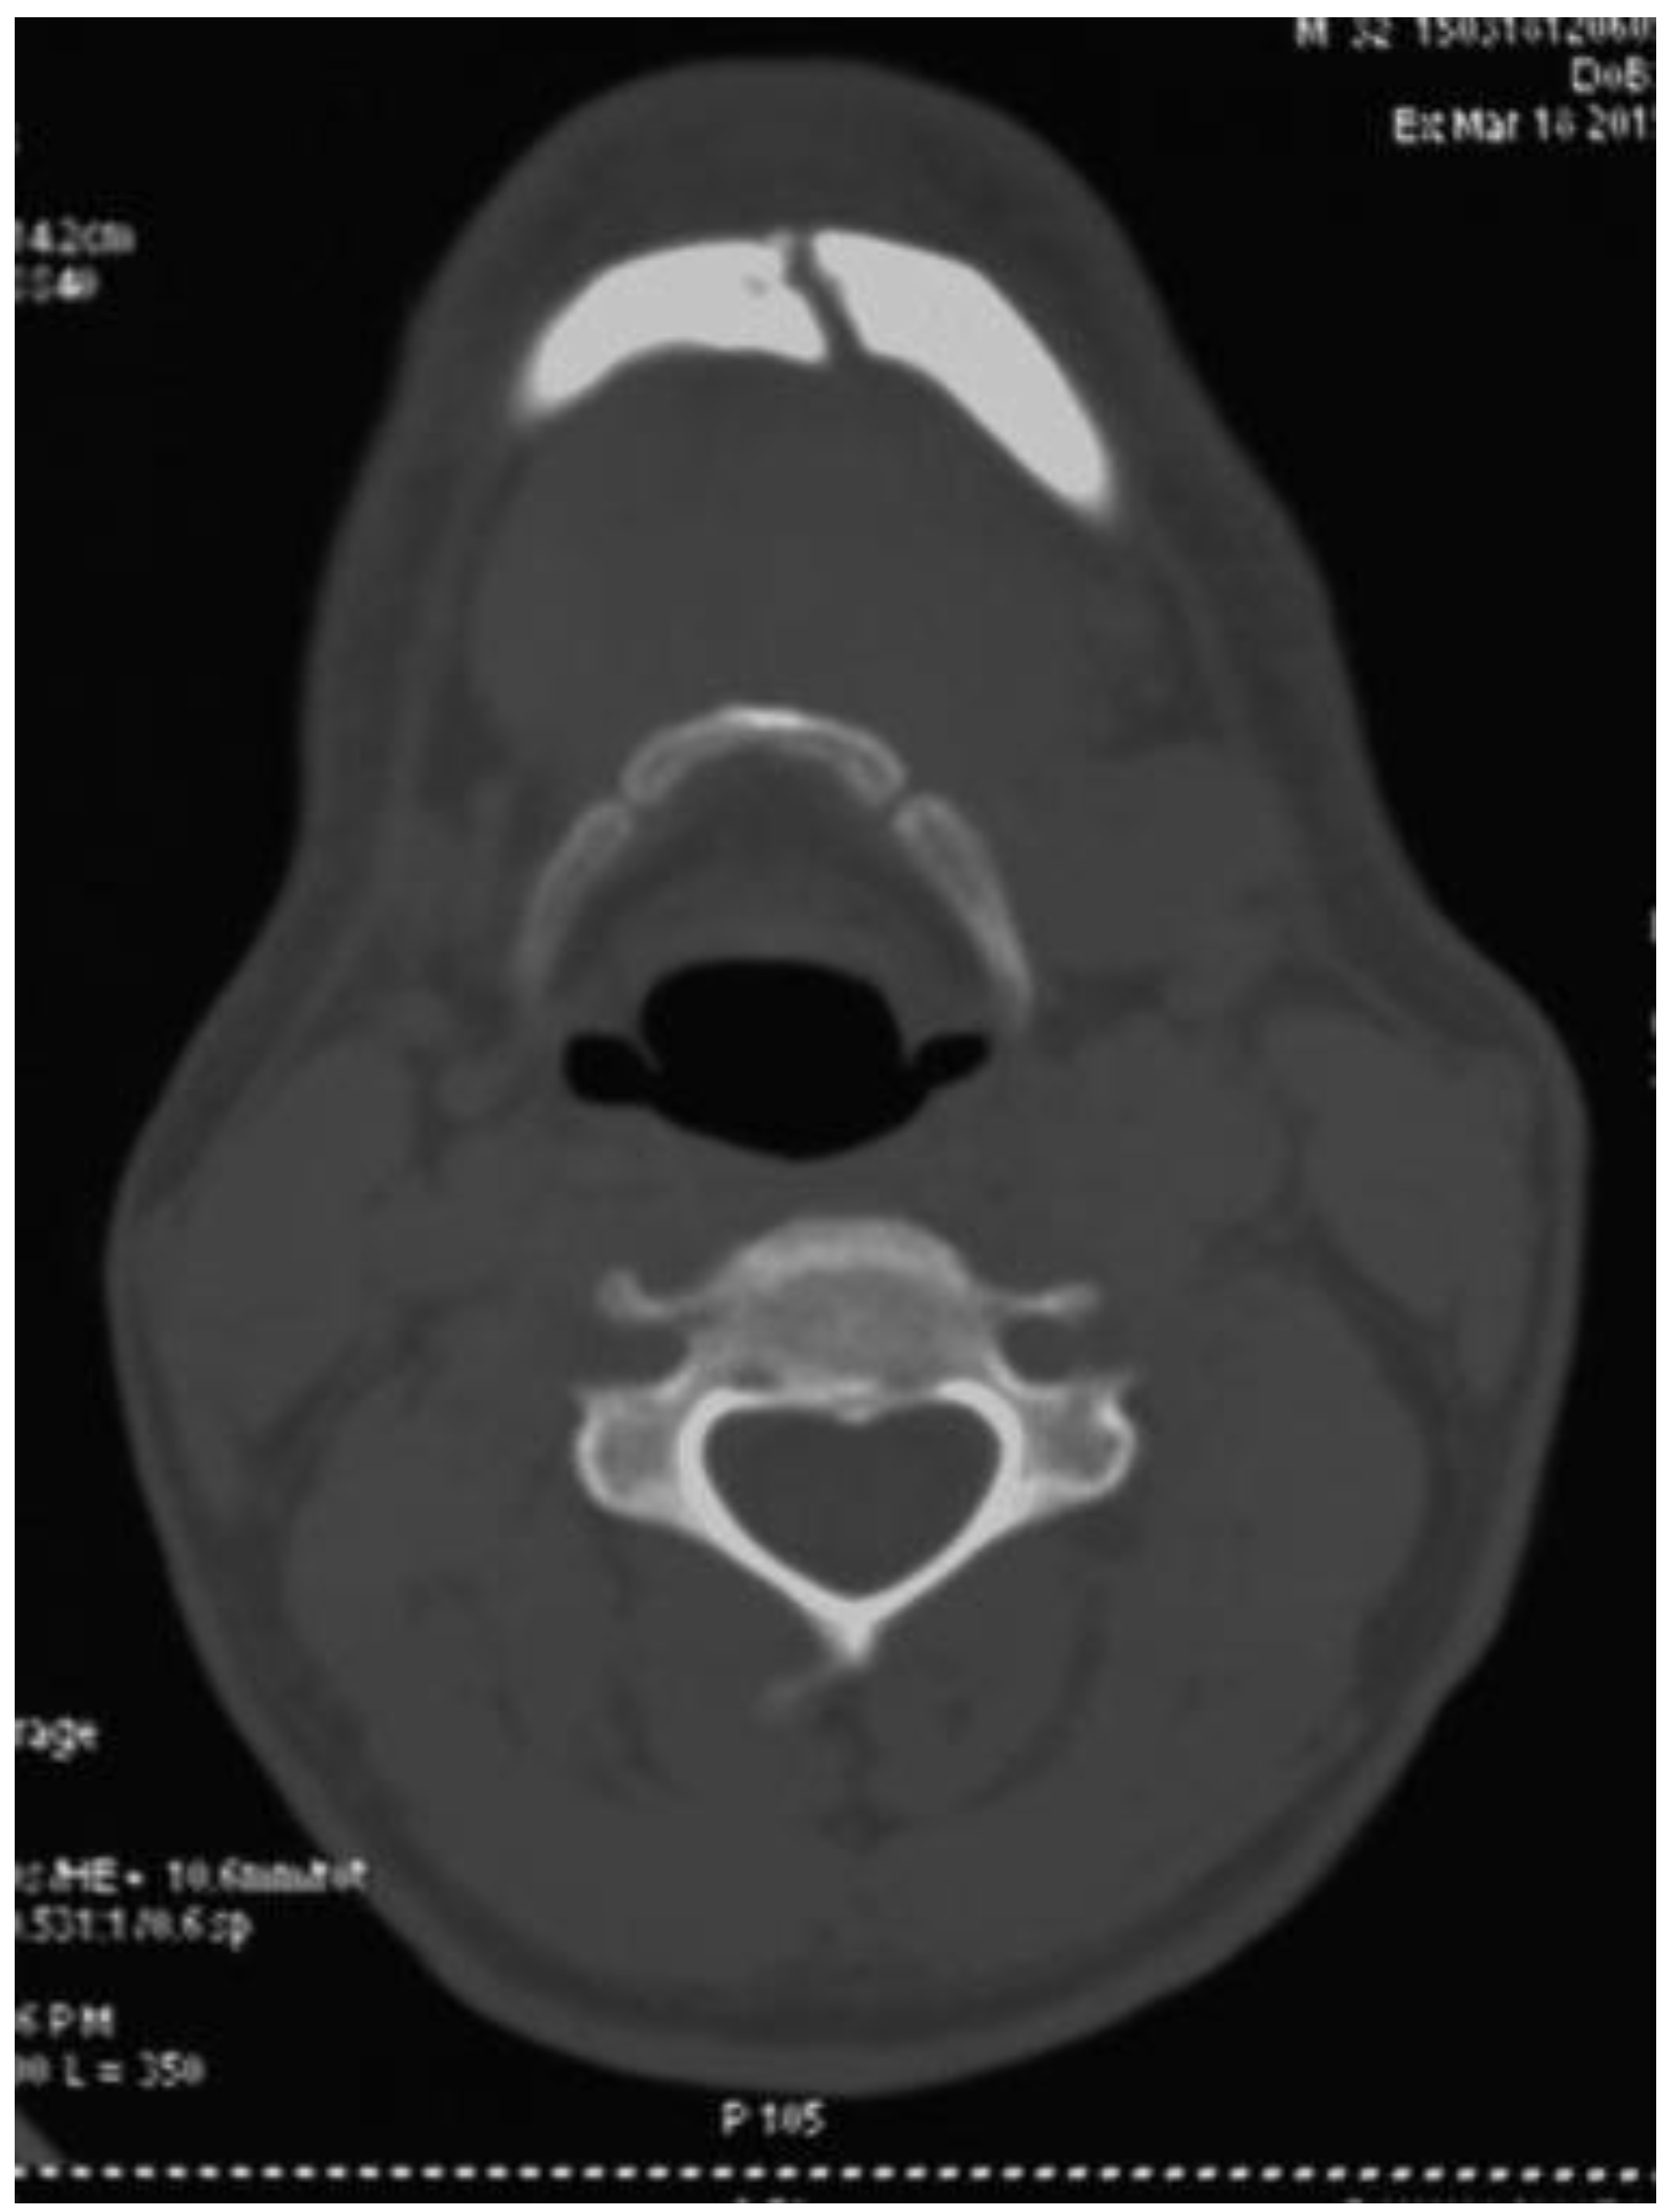

Six out of seven patients showed good anatomical reduction on postoperative CT scans (Figure 6, Figure 7, Figure 8 and Figure 9) and orthopan-tomograph (Figure 10, Figure 11, Figure 12 and Figure 13). On regular follow-up at 3 weeks, 3 months, and 6 months, and 1 year, no evidence of wound dehiscence, discrepancy in occlusion, or lower border malalignment was seen (Figure 14).

Figure 6. Case 1: Preoperative CT scan of axial section showing interforaminal fracture of right side mandible.